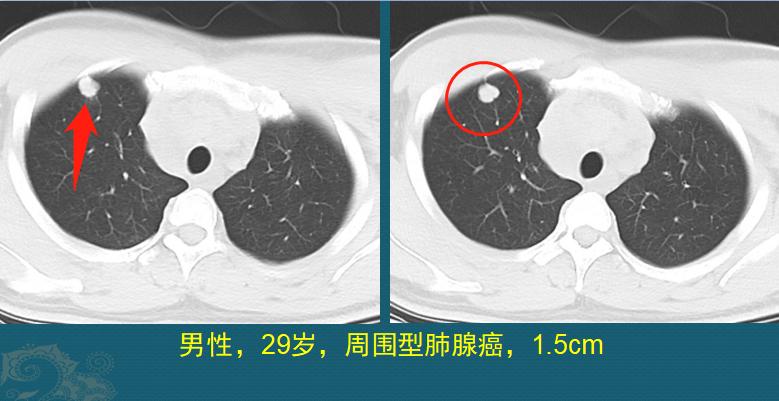

呼吸科医生摸了摸,默默给他开了胸部CT,发现1.5cm的肺癌:

这是一个不规则实性肺结节,表面有分叶,长径只有1.5cm,却已经发生了纵隔、颈部多发淋巴结转移,肩胛骨转移,没有手术机会了。

我们看下图箭头,这个结节是周围型,边缘贴近前壁胸膜,癌细胞顺着胸膜上丰富的淋巴管道漂流到纵隔、颈部淋巴结,鸠占鹊巢发展壮大了。右图箭头是明显增大的纵隔淋巴结,与大血管都分界不清了: